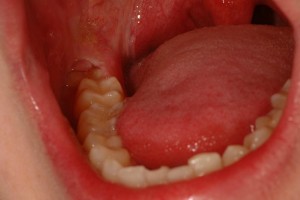

Воспаление мягких тканей вокруг прорезывающегося зуба (чаще третьих нижних моляров).

Клиническая картина характеризуется сначала наличием боли в области прорезавшегося зуба и воспалением слизистой оболочки над этим зубом («капюшон»). Вскоре появляется затруднение при открывании рта (контрактура), приводящее к полному смыканию челюстей. Нарастание боли совпадает с распространением воспаления на соседние отделы ретромолярной области, глотки, подчелюстной области, щеки, шеи. Возникает регионарный лимфаденит, ухудшается общее состояние больного, температура тела повышается до 38° С и выше.

Лечение. Под местным обезболиванием иссекают слизистую оболочку над прорезывающимся зубом, обнажая полностью его жевательную поверхность. Тампоном предупреждают повторный «наплыв» слизистой оболочки на коронку зуба. При развитии периостита необходимо вскрыть гнойник.